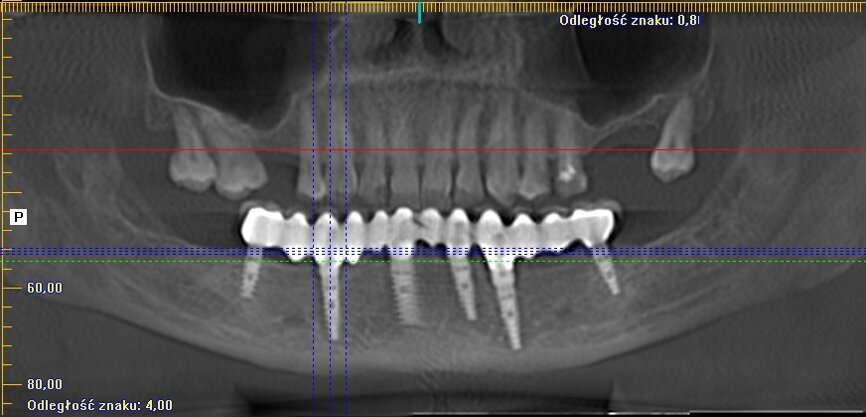

Implanty zostały wprowadzone wg zasady przylegania w cieniu, tzn. wszczep musi na całej swojej długości mieć kontakt z którąś ze ścian zębodołu 1-2 mm subkrestalnie (Ryc. 4). W przypadku konieczności użycia membrany, musi ona mieć możliwość rozpostarcia się nad ubytkiem kostnym i implantem tak, aby odległość pomiędzy membraną a wszczepem nie była mniejsza niż 2 m (Ryc. 3). Wszczepy o

charakterystyce agresywnej wprowadzono w okolice zębów: 36, 34, 32, 42, 44 i 46.

przygotowanej wcześniej protezie czasowej metodą bezpośrednią. Czasowe uzupełnienie protetyczne osadzono, używając cementu tymczasowego (Ryc. 5 i 6). Zlecono wykonanie zdjęcia techniką CBCT (Ryc. 7). Wizytę kontrolną wyznaczono następnego dnia, a szwy zostały usunięte po 10 dniach.

zlecono też wykonanie kontrolnego zdjęcia CBCT i następnego po 12 miesiącach (Ryc. 10 i 11).

W kwietniu 2017 r. został wykonany status periodontologiczny pozostałego uzębienia i wszczepionych implantów (Ryc. 12) i ponowne badanie CBCT (Ryc. 13- 15). Stan 3 lata po zabiegu przedstawiono na rycinach 16-18. Pacjentka jest ujęta w programie Recall w cyklu 6-miesięcznym od dnia wykonania zabiegu.